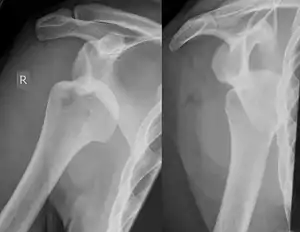

A Hill–Sachs lesion, or Hill–Sachs fracture, is a cortical depression in the posterolateral head of the humerus. It results from forceful impaction of the humeral head against the anteroinferior glenoid rim when the shoulder is dislocated anteriorly.

| Anterior shoulder dislocation on X-ray with a large Hill–Sachs lesion | |

Diagnosis can be suspected by history and physical examination which is usually followed by imaging. Because of the mechanism of injury, apprehension of anterior dislocation is common with provocative maneuvers. Hill–Sachs lesions have been classified as "engaging" or "non-engaging", with engaging lesions defined by the ability of the glenoid to sublux into the humeral head defect during abduction and external rotation. Engaging dislocations have a higher risk of recurrent anterior dislocation, and their presence can help guide surgical management.[2] Imaging diagnosis conventionally begins with plain film radiography. Generally, anteroposterior (AP) radiographs of the shoulder with the arm in internal rotation offer the best yield while axillary views and AP radiographs with external rotation tend to obscure the defect. However, pain and tenderness in the injured joint make appropriate positioning difficult and in a recent study of plain film x-ray for Hill–Sachs lesions, the sensitivity was only about 20%. i.e. the finding was not visible on plain film x-ray about 80% of the time.[3]